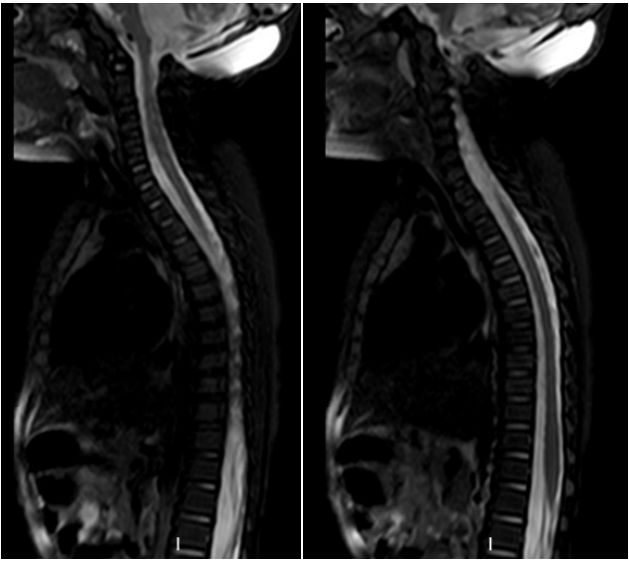

浙江大学医学院附属儿童医院门诊头颅磁共振提示:后颅窝占位,梗阻性脑积水。

图1. 头颅MR平扫:a,b为T1加权像,c,d为T2加权像,e为矢状位T1。见后颅窝巨大实性均质肿块,伴幕上严重脑积水。